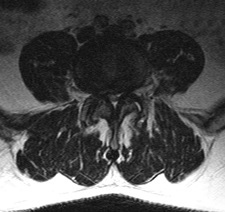

The narrowing of the spinal canal, called spinal stenosis, can happen as a result of the degeneration of both the facet joints and the intervertebral discs. In this condition, bone spurs, called osteophytes, which develop because of the excessive load on the intervertebral disc, grow into the spinal canal.

The facet joints also enlarge as they become arthritic, which contributes to a decrease in the space available for the nerve roots. The ligaments of the spinal column, especially the ligamentum flavum, become stiff, less flexible and thicker with age, which also contributes to spinal stenosis. These processes narrow the spinal canal and may begin to impinge and put pressure on the nerves roots and spinal cord, creating the symptoms of spinal stenosis.

Stenosis may occur in the central spinal canal (central stenosis) where the spinal cord or cauda equina are located, in the tract where the nerve root exits the central canal (lateral recess stenosis) or in the lateral foramen (foraminal stenosis) where the individual nerve roots exit out to the body.

A computed tomography (CT or CAT) scan provides excellent visualization of the bony anatomy of the spinal column and is an indispensable tool for determining where the stenosis is located. This test is often performed in conjunction with a myelogram, which involves injecting dye into the space occupied by the spinal cord and nerve roots to determine how well the cerebrospinal fluid is able to travel along the nerve roots. An EMG or electromyographic test may help to determine which nerve root in particular is not working normally in the situation where several nerve roots may be involved.